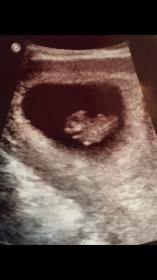

Would anybody want to guess on my ultrasound. It was an abdominal ultrasound at 8+1. It isn't in the picture , but at the ultrasound you could see the yolk sac off to the right of the baby.Attachment 33976